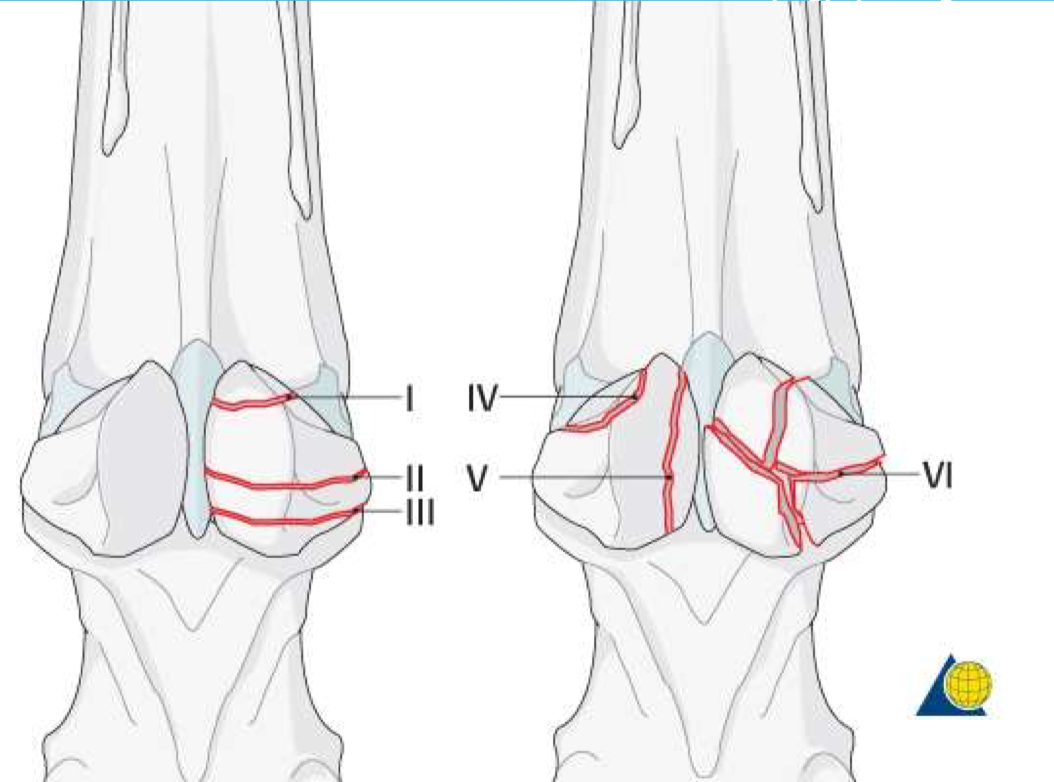

VI represents a ________ fracture of the proximal sesamoid bones

comminuted

III represents a ________ fracture of the proximal sesamoid bones

Base

I represents a ________ fracture of the proximal sesamoid bones

Apical

V represents a ________ fracture of the proximal sesamoid bones

Sagittal (Axial)